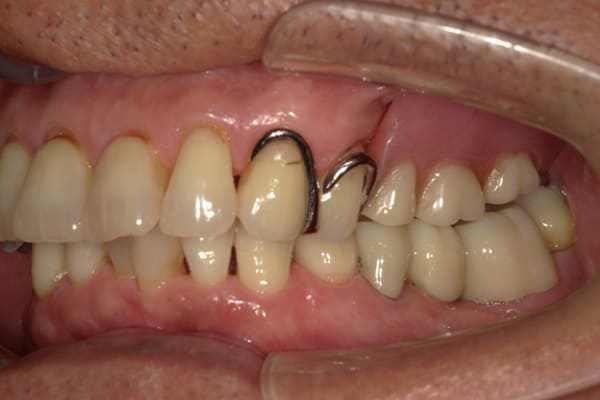

症例レポート[CASE.12]

色んな歯医者で何度も作ったが咬めない

-

- 女性(50代)

- 主訴

- 入れ歯が合わない、色んな歯医者で何度も作ったが咬めない、もう歯は抜きたくない

- 治療

- 下顎精密金属床部分入れ歯

- ジルコニアクラウン 1歯

- 治療期間

- 約3か月間

- 費用

- 下顎精密金属床部分入れ歯:55万円

- ジルコニアクラウン:11万円×1歯

合計:66万円(税込)

装着中の入れ歯は、歯茎に接する面積が小さく、強い咬む力を入れ歯が接する歯肉では負担できずお痛みが出ている状態でした。

保険の型取り

自費の型取り

保険の入れ歯の場合、既成のトレーを用い、ピンクの材料で型を取り入れ歯が出来上がります(保険の型取り)。

ピンクの材料は変形量が大きく、お口の中の状態を正確に入れ歯に再現することはできないため、今回はまず初めにピンクの材料で一度、型をお取りし、その型をもとに、患者様専用のトレーを作製、舌や頬の動きを印記(緑の部分)し、変形量が極めて少ないシリコンを用いて型どりを行いました(自費の型取り)。

同じお口の中ですが、2つの写真で全く形が違うのが分かります。

この型に合わせて入れ歯が出来上がるため、よりお口の中を正確に再現することで、お痛みがでずらい適切な入れ歯をつくることが可能になります。

この入れ歯のバネは、RPIクラスプと呼ばれ、保険のバネと違い、バネをかける歯に極力負担をかけない設計となっているバネになります。このバネにより歯の寿命を長くすることが期待できます。